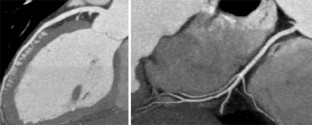

Abb. 4